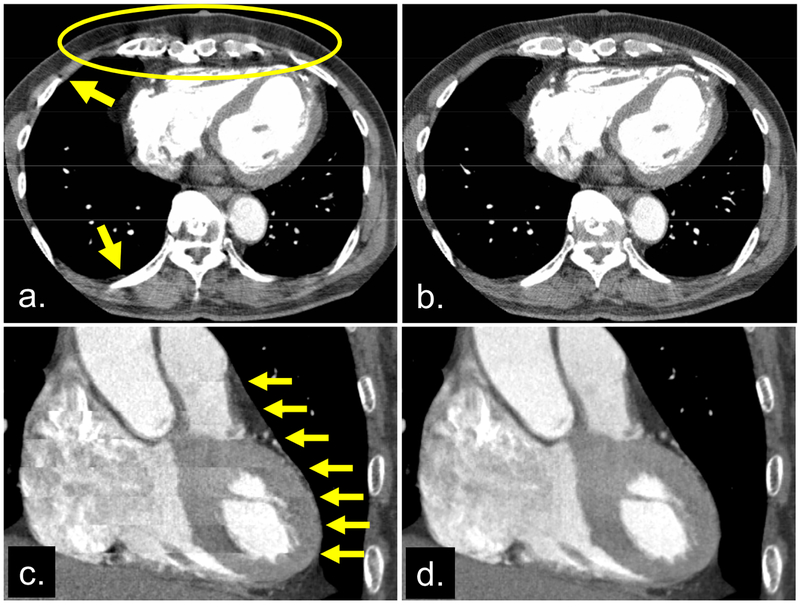

Fig 3.

Images reconstructed from the same cone-beam projection data. Axial images reconstructed by the fan-beam algorithm (a) and the cone-beam algorithm (b), respectively. Shading artifacts near the stationary ribs (indicated by arrows in [a]) imply that shading in the circle might be due to cone-beam artifacts, not perfusion defects or motion artifacts. This point was proved by applying the cone-beam algorithm (that accurately takes into account the cone-angle) (b). Coronal images reconstructed without (c) and with (d) the cardiac banding artifact correction algorithm [2]. The image without correction (c) exhibited discontinuous banding artifacts (arrows), which are corrected in (d).

Shadings may appear near the spine and ribs when the cone-beam geometry is not correctly handled. The shadings are problematic because they make the detection of perfusion defects difficult (Figures 3a and 3b).

Banding artifacts are longitudinal discontinuities that are easily observed in coronal, sagittal, or curved cross-sectional images (Figure 3c). These artifacts result in nondiagnostic images [2].

Solutions include having the patient take a β-blocker to reduce heart rate variation and, if available, applying gating methods that are robust against heart rate variation [2,3] (Figure 3d) or that use images to find optimal gating phases specific to each heartbeat [7].